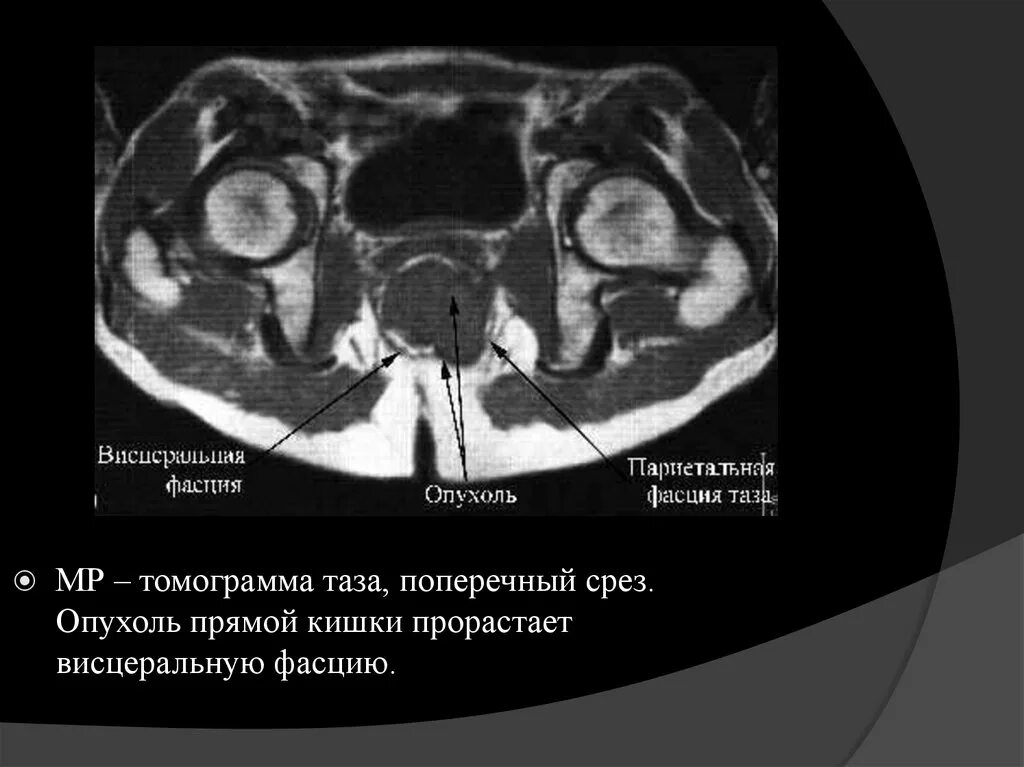

Рак прямой кт